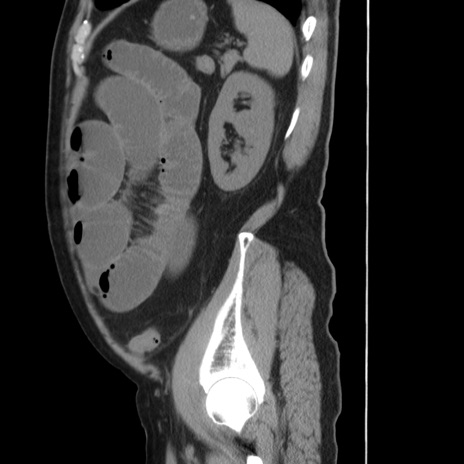

症例20(矢状断像)

【症例】 60歳代男性

【主訴】 腹部膨満、嘔吐

【現病歴】5日前頃より倦怠感を認め食事量減少し4日前の朝嘔吐、食事摂取困難となった。 3日前近医受診し点滴施行され整腸剤などを処方された。 当日他院を受診し、腹部膨満著明、炎症反応の上昇(CRP10.8、WBC11200)あり、紹介受診となる。

【身体所見】 意識JCS1 受け答えがはっきりしないBP 111/57mHg、 P 67bpm、、BT35.2°C、SpO2 97%(RA)、 腹部:膨隆、打診で鼓音あり、全体的に圧痛有り、腸蠕動音(-)、反跳痛ははっきりせず。

【データ】WBC 11400、CRP 14.20